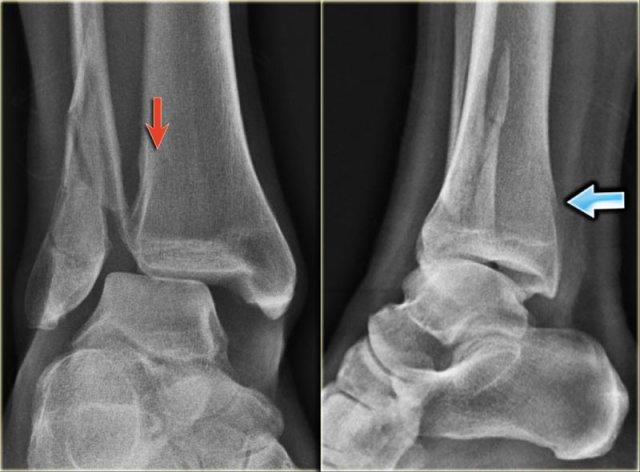

- Tái khám

Trên phim chụp cổ chân không có dấu hiệu gãy xương chéo của mắt cá ngoài, do đó chúng ta có thể loại trừ gãy xương Weber B.

Vẫn còn khả năng gãy xương Weber C giai đoạn 4, tức là đứt hoặc bong gân phía trong, gãy xương mác cao và cuối cùng là gãy mắt cá sau.

Khi tái khám, bạn nhận thấy hình ảnh bong điểm bám tinh tế của mắt cá trong (mũi tên đỏ), đây là giai đoạn 1.

Cũng lưu ý tình trạng sưng nề phần mềm ở phía trong (mũi tên xanh)

Các phim X-quang bổ sung của chi dưới được chỉ định và cho thấy gãy xương mác cao, tức là Weber C giai đoạn 3, còn được gọi là gãy xương Maisonneuve.

Final report

Weber C fracture stage 4.

This is un unstable ankle injury that needs surgical repair.